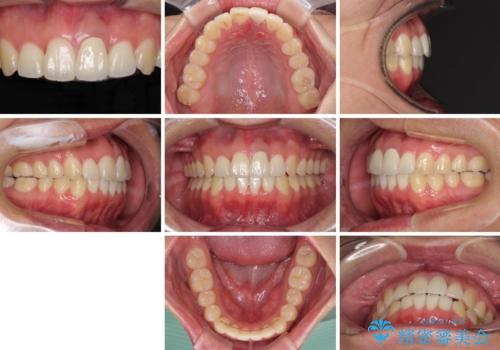

前歯の歯並びとクラウンを改善 インビザラインとオールセラミック

- 前歯の歯並びと不自然な色をした前歯のクラウンを気にして来院された患者様です。

上下前歯の歯列不正はインビザラインにより歯列を整え、その後に、前歯をオーダーメイドタイプのオールセラミッククラウンにて補綴治療することとしました。

初診時には、歯並びを整えることのみを検討されていましたが、歯列が整うにつれて不自然な色合いが気になるようになり、矯正治療を行ってから補綴治療をする計画を受け入れてくださいました。

口元の印象が明るく変わり、患者様には大変満足していただきました。